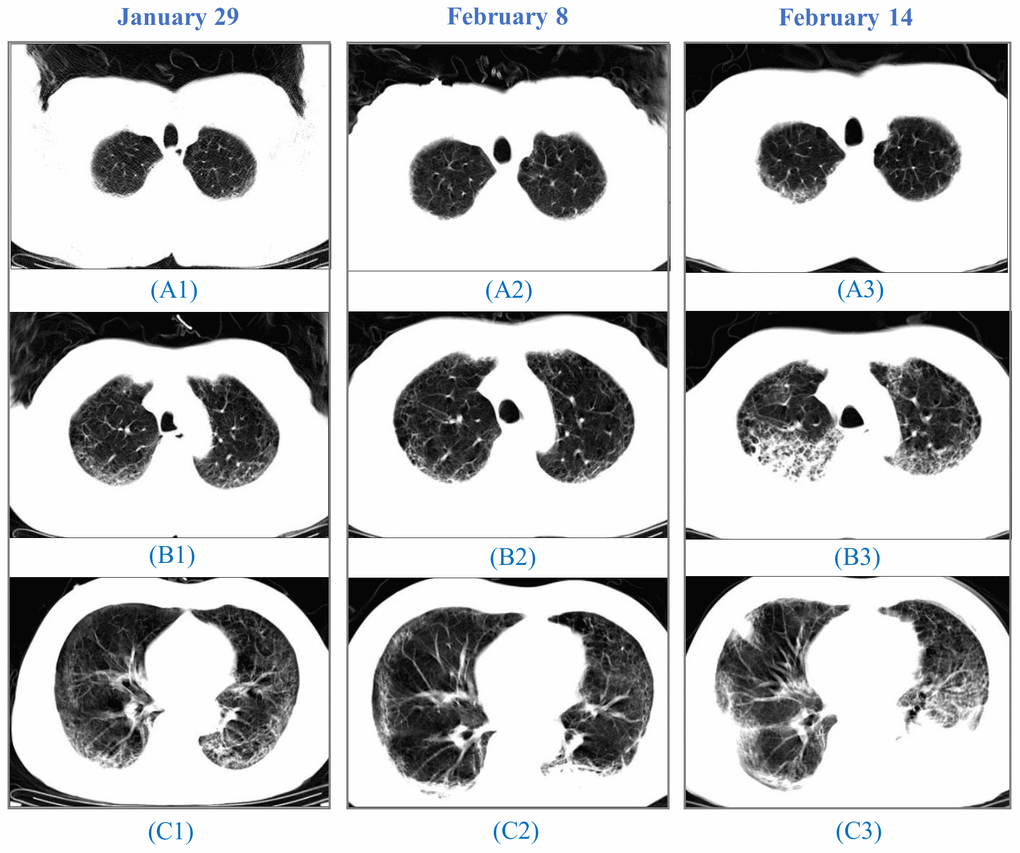

Comparisons of CT diagnostics in younger and older patients revealed no difference in the risk of abnormal lungs (p=0.972). Two males were severely ill during hospitalization and died thereafter. CT images showed the accumulation of ground-glass opacities and pulmonary consolidation during the disease progression (Figure 2).

Figure 2. CT images from a 64-year-old man. A 64-year-old man, who had a fever and pneumonia, was suspected as the SARS-CoV-2 carrier on January 28 and confirmed on January 30. (A1), (B1) to (C1): On January 29, initial CT scans at the hospital admission showed multifocal ground-glass opacity (GGO) and reticulation, predominantly in the subpleural areas of both lungs. (A2), (B2) to (C2): On February 8, CT images indicated progressing GGOs. Newly-appeared patchy and core-like consolidation were visible in lower lobes of both lungs. The patient showed high fever, cough, blood in the sputum, reduced SpO2, and a sign of heart failure. (A3), (B3) to (C3): On February 14, CT images showed progressing lesion with multiple newly-appeared GGO and consolidation. Irregular interlobular septal thickening was observed in the upper lobe of the right lung. The patient passed away on February 15.